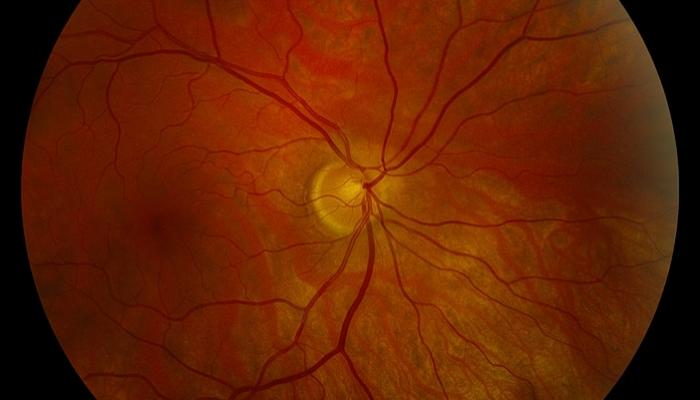

Атрофия зрительного нерва Лебера: Симптомы и лечение